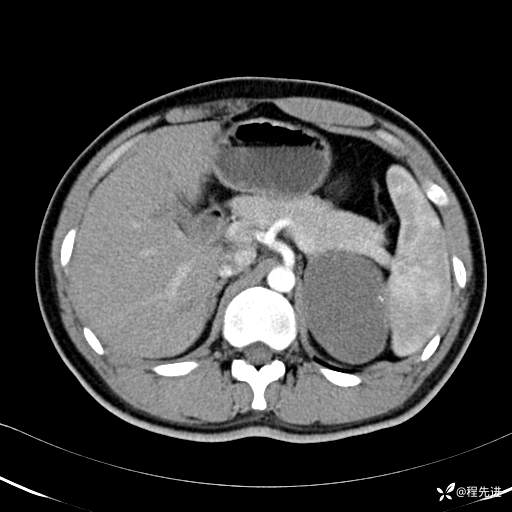

【腹盆】特别精彩病例|体检发现的左侧腹膜后占位期待您的精彩解读

患者年龄:25岁

简要病史:体检发现

CT平扫:(CT值:平扫,27HU,动脉期,27HU,门静脉期,31HU,平衡期,32HU)

CT增强:

门静脉期: